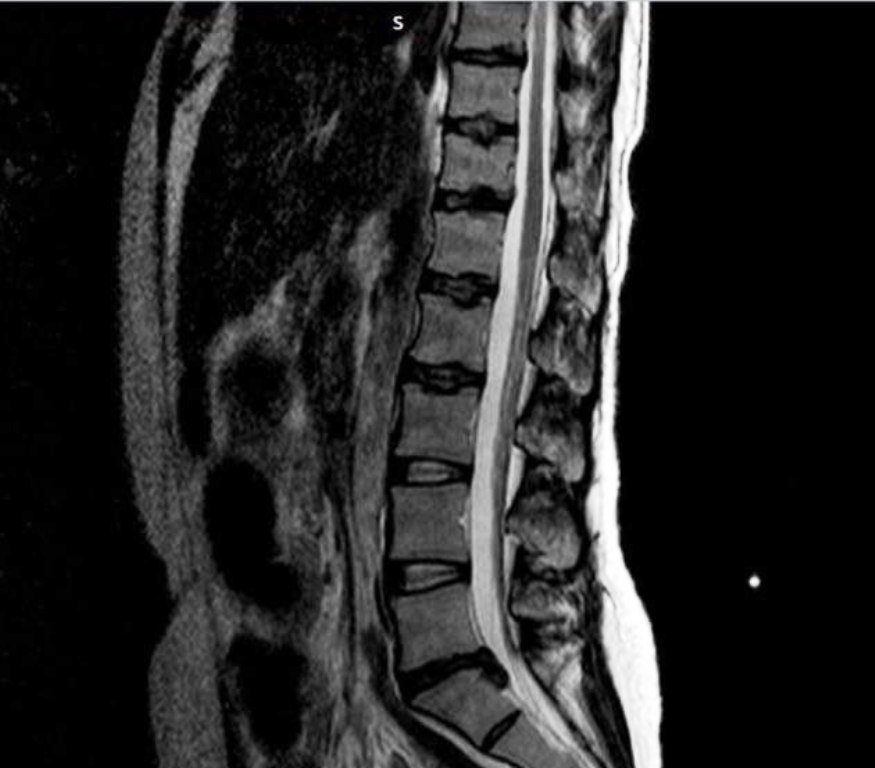

В неврологическое отделение Каширской больницы была госпитализирована 37-летняя женщина, которая жаловалась на сильные боли в спине, мешавшие ей передвигаться самостоятельно. По информации учреждения, женщина предоставила снимки МРТ пояснично-крестцового отдела позвоночника, по которым определялась межпозвоночная грыжа между пятым поясничным позвонком и первым крестцовым. Это состояние, когда диск выпячивается и оказывает давление на нервы, вызывая сильную боль и дискомфорт. В ходе дополнительных обследований врачи выявили у женщины анемию средней тяжести и эрозивный гастрит, усложнившиеся из-за неконтролируемого приема обезболивающих препаратов. Это вынудило врачей отложить операцию и пересмотреть план лечения.

Вместо операции пациентке была проведена паравертебральная анестезия поясничной области. Этот метод предполагает введение анестетика в область вокруг позвонков, что приводит к временному блокированию передачи нервных импульсов от позвоночника к мозгу, и значительно снижает болевой синдром. Процедура позволила пациентке вновь ходить, после чего она была переведена в терапевтическое отделение для лечения и восстановления.